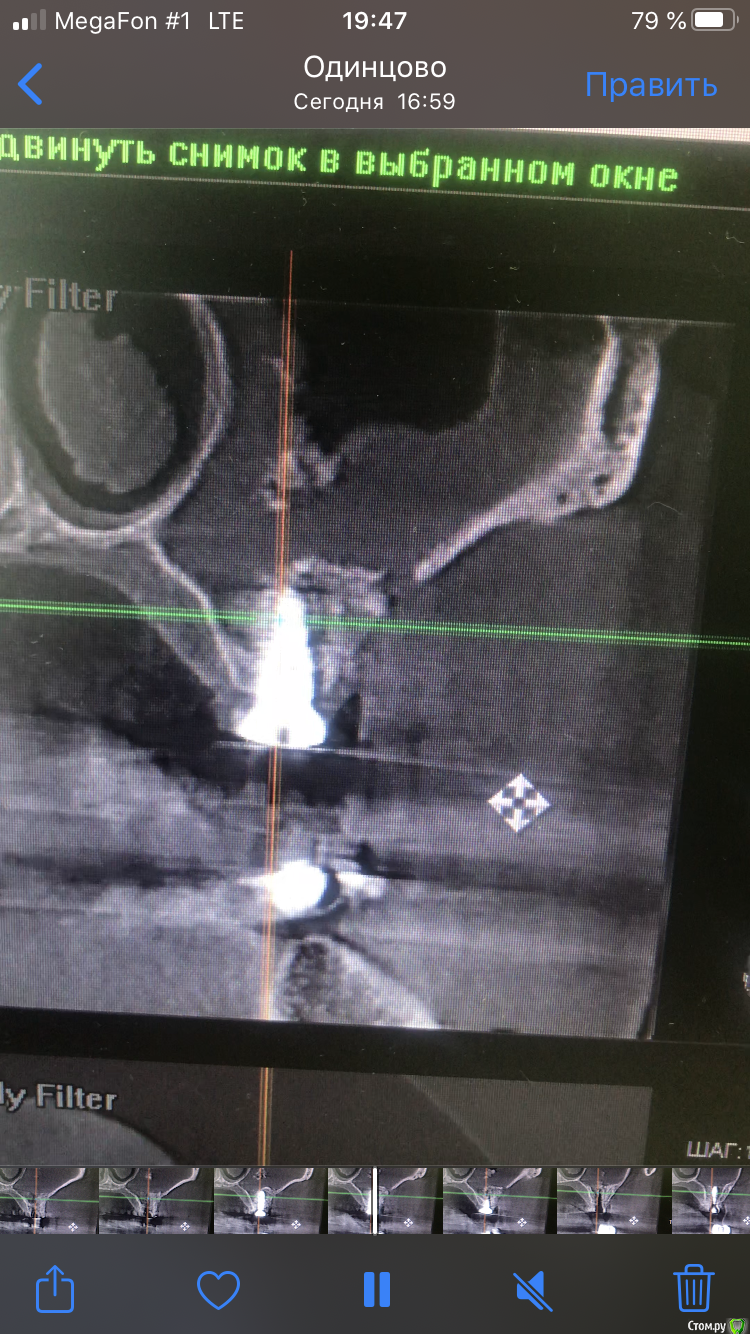

dave09090 Опубликовано 11 августа, 2020 Поделиться Опубликовано 11 августа, 2020 (изменено) Приветствую коллеги. 4-ре мес назад была проведена операция ОСЛ с одномоментной имплантацией . Послеоперационный период прошёл хорошо без болей и выделений. Неделю назад позвонила и сказала что чувствует имплантат при беге или стуке ногой. Поросил сделать кт. И там такое. Перфорацию почему то во время операции не углядел видимо. Что посоветуете делать ? Изменено 11 августа, 2020 пользователем dave09090 Ссылка на комментарий

stommm Опубликовано 11 августа, 2020 Поделиться Опубликовано 11 августа, 2020 Вижу 2 варианта: лор через естественное соустье расширив его убирает свободно лежащий графт. Остальное, если плотное, оставить и дать через пару месяцев нагрузку на имплант времяшкой. Самому сделать доступ повыше, убрать графт и далее все то же самое что и в первом варианте. Если графт вокруг импланта мягкий, то либо ждать еще, либо убирать все 1 Ссылка на комментарий

L.E.S.I.K. Опубликовано 12 августа, 2020 Поделиться Опубликовано 12 августа, 2020 (изменено) Оставлять так в любом случае нельзя?Нет. Графт, лежащий в синусе - инородное тело, и как следствие, будет поддерживать течение воспалительного процесса. Изменено 12 августа, 2020 пользователем L.E.S.I.K. 1 Ссылка на комментарий

Александр07 Опубликовано 13 августа, 2020 Поделиться Опубликовано 13 августа, 2020 Если Имплант стабилен и внешне все норм я бы через Лора эндоскопически, пусть вычистит , а/б, и наблюдать, если не пройдёт тогда уже самому оставшееся проще убрать будет при необходимости Ссылка на комментарий

dave09090 Опубликовано 14 августа, 2020 Автор Поделиться Опубликовано 14 августа, 2020 спасибо. имплантаты стабильны торг проверял 35. Ссылка на комментарий